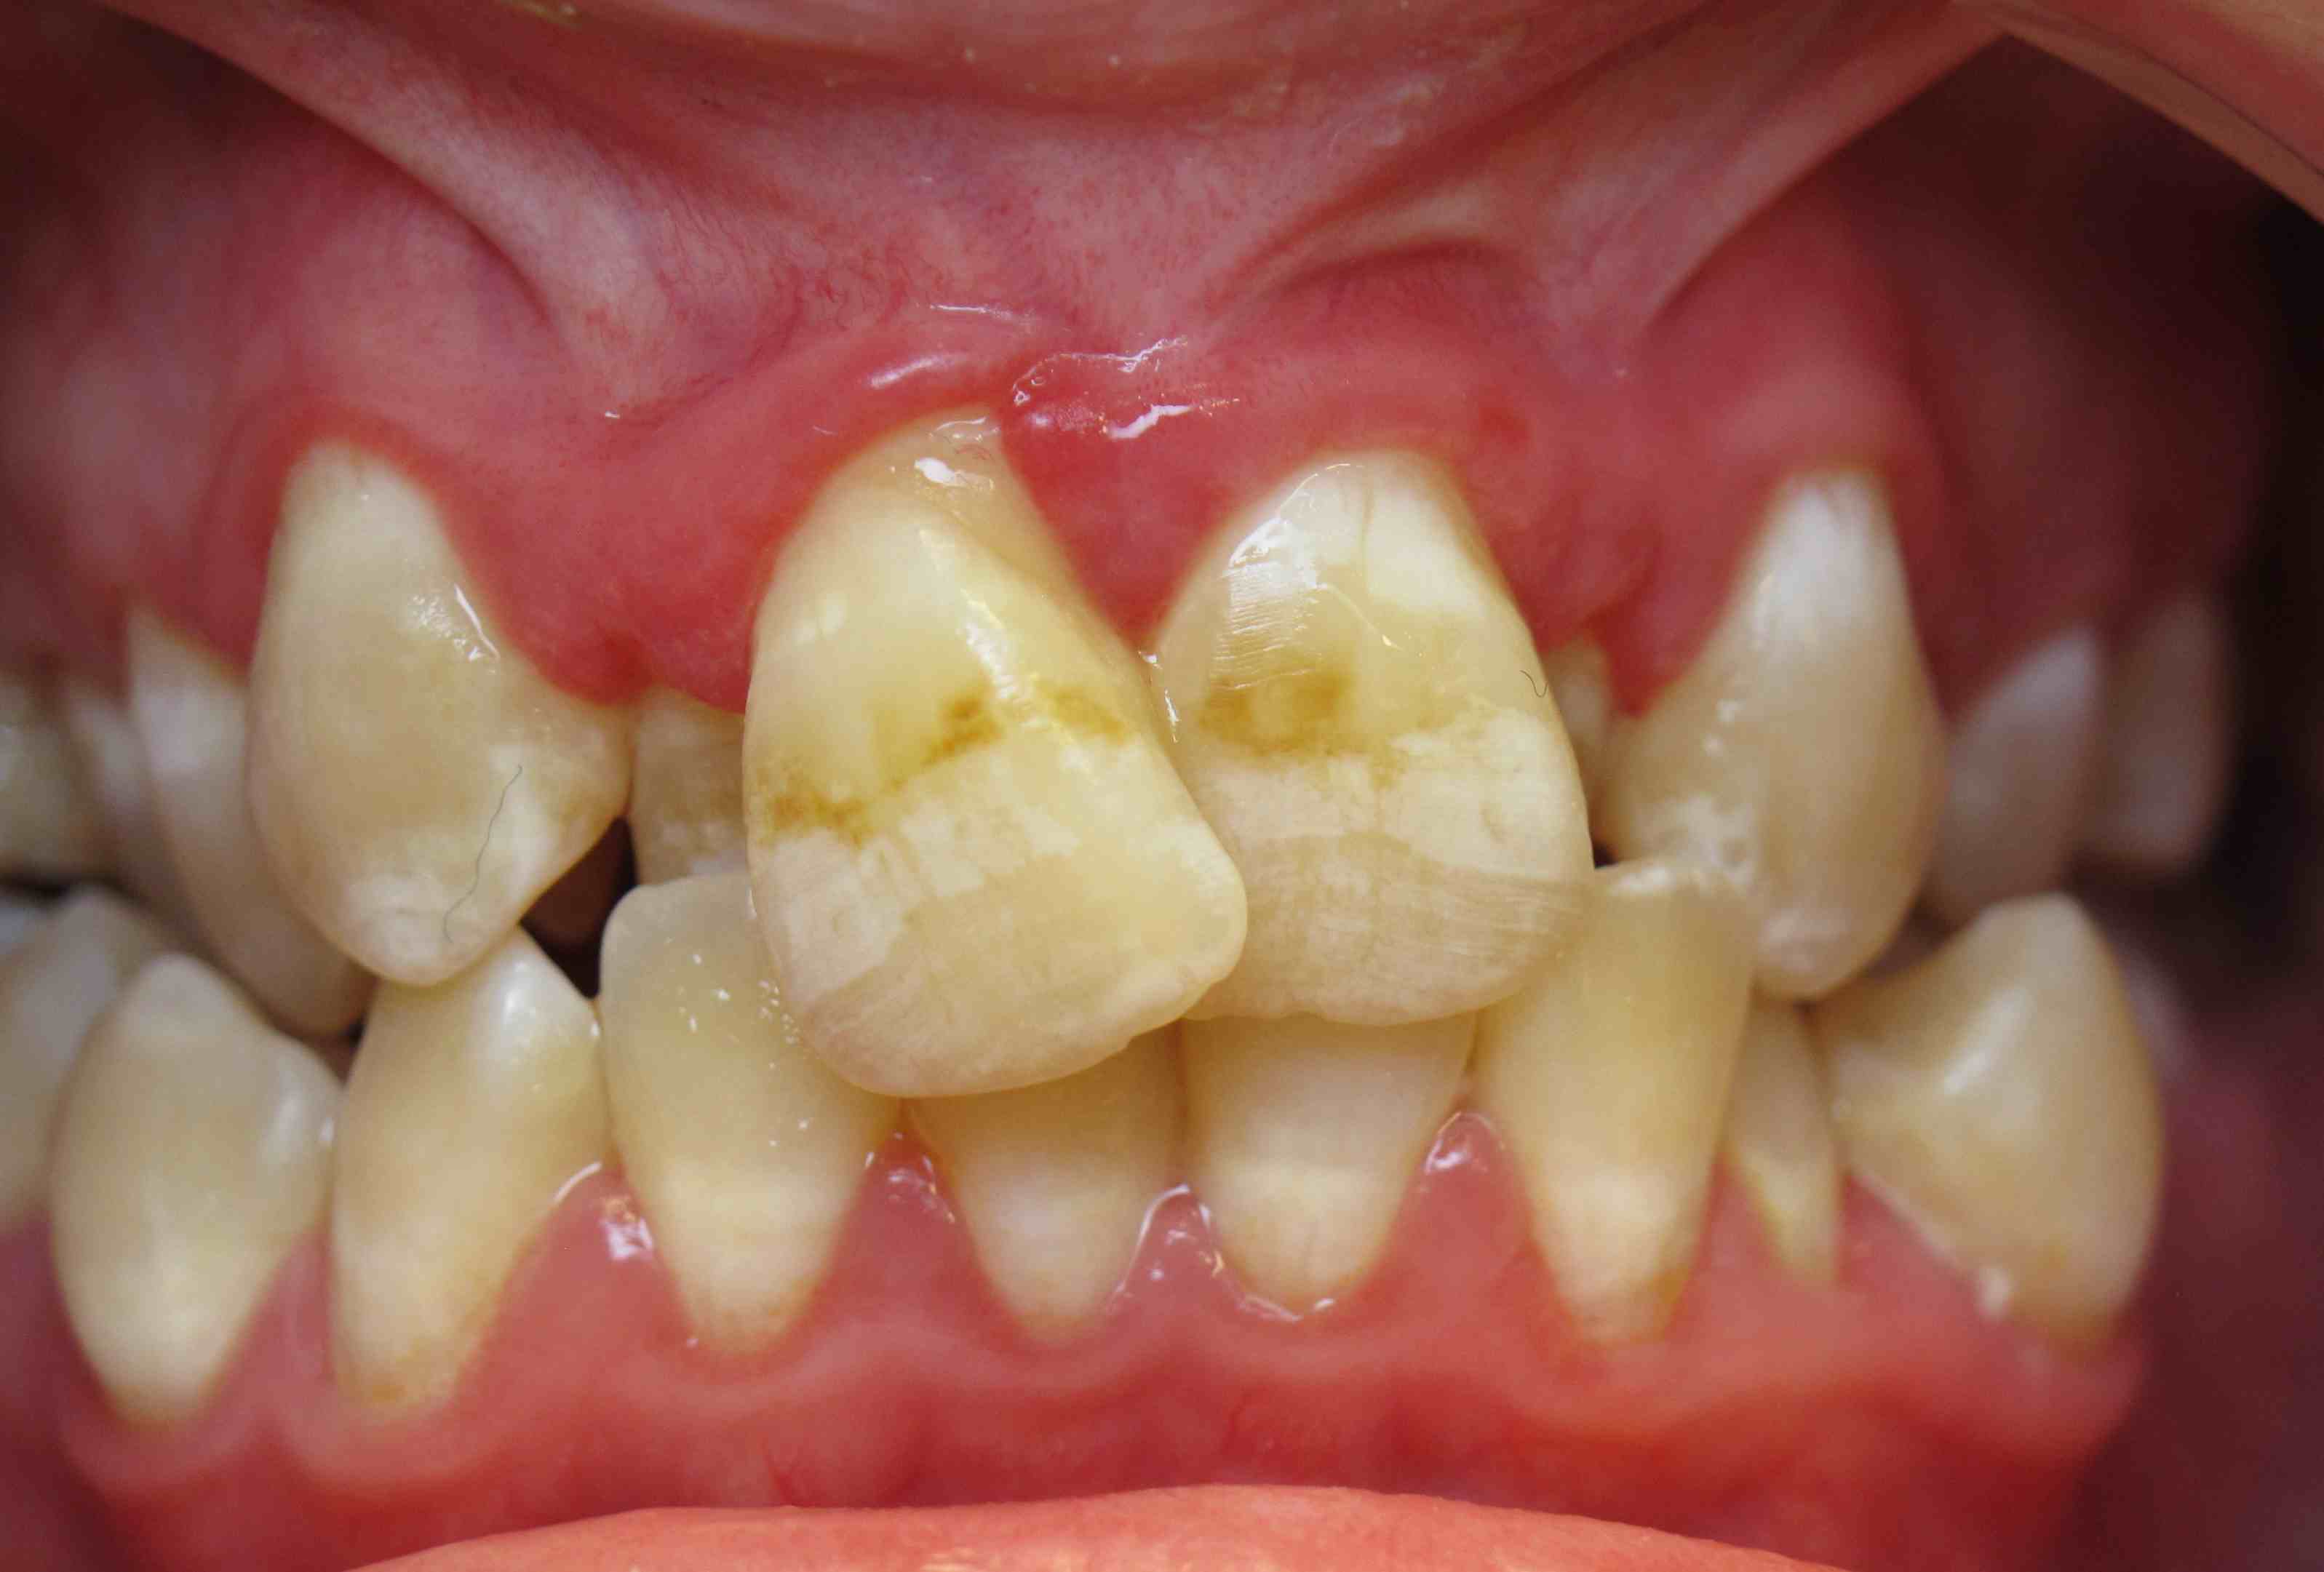

Pic.16. Mesial position of tooth 11 with lack of space in the dental arch.